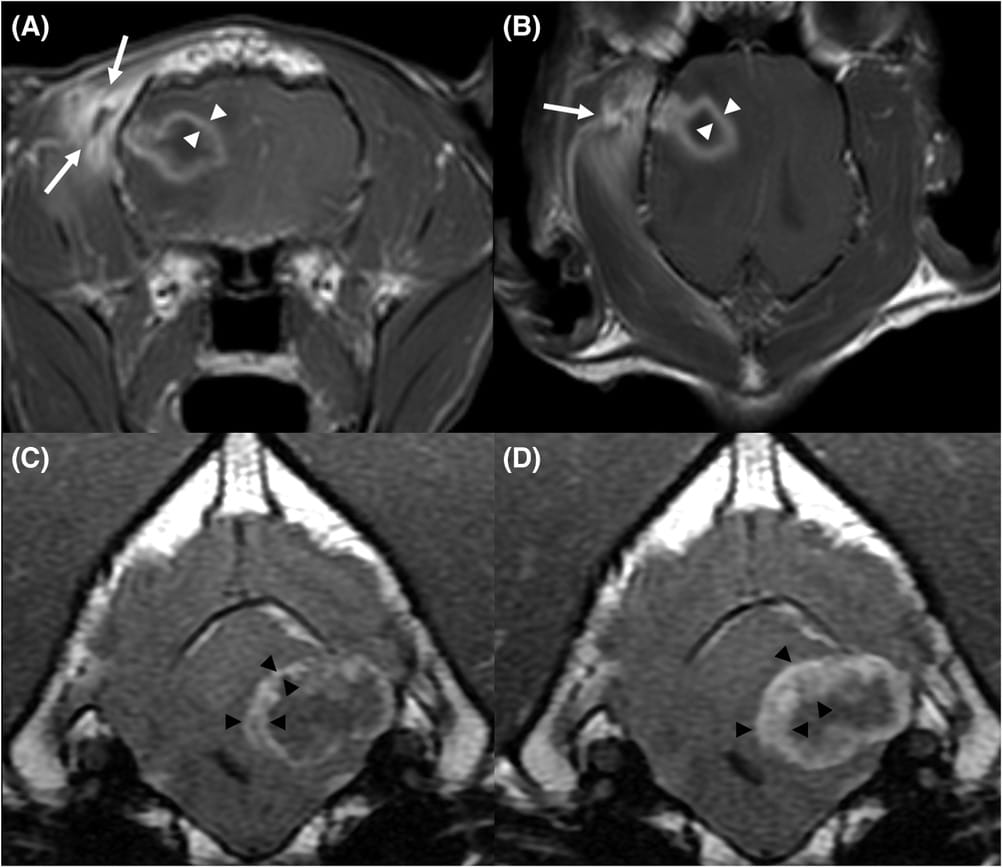

Immediate postcontrast T1W transverse (A) and dorsal delayed postcontrast T1W (B) images (1.5 T, transverse T1W FSE TR 500, TE 13) of a 9-year-old male neutered, DLH cat with a right temporo-parietal lobe abscess secondary to a bite wound with temporal myopathy (arrows). Despite the different acquisition planes, the thickness of the abscess capsule does not increase over time (white arrowheads). Immediate postcontrast T1W FLAIR (C) and delayed postcontrast T1W FLAIR (D) transverse images (1.5 T, transverse T1W FLAIR FSE TR 2560, TE 26, TI 1013) of a 9-year-old, female spayed, Labrador Retriever with a left cerebellar ring-enhancing glioma. Note the conspicuous central progression (black arrowheads) of the enhancement on the delayed postcontrast sequence

Results: The study found that brain abscesses showed a more homogeneous signal on T1W and T2W sequences than ring-enhancing gliomas. A peripheral hypointense halo on T2W and T2*W GE sequences was significantly associated with brain abscesses rather than ring-enhancing gliomas. On postcontrast T1W sequences, abscesses showed a more even ring-enhancing capsule compared to ring-enhancing gliomas. Ring-enhancing gliomas were more likely to have a progressive central enhancement on T1W delayed postcontrast sequences.

Conclusions: The study concluded that even if several overlapping MRI features between ring-enhancing gliomas and brain abscesses exist, some features can help to prioritize the MRI diagnosis. The presence of a homogeneous T1W or T2W signal intensity, a T2W or T2*W GE peripheral hypointense halo and an even enhancing capsule may indicate a brain abscess. The central progression of the enhancement on delayed postcontrast T1W sequences is indicative of glial neoplasia